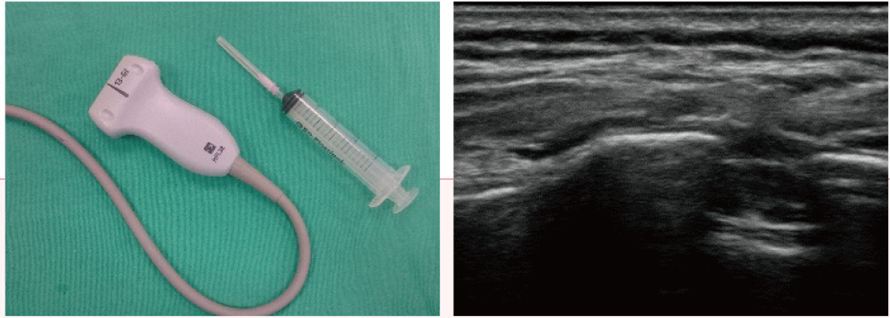

神經止痛術

神經止痛術,是將小兒病人於全身麻醉狀態下,把局部麻醉劑或止痛藥物,依據解剖相關位置,輔以影像(如:超音波)導引,將藥物注射浸潤於神經、肌肉、肌腱或關節腔周圍,來減緩手術後疼痛,止痛效果十分顯著。使用神經止痛術,可明顯減少靜脈止痛藥物(如:嗎啡)之用量,進一步降低靜脈止痛藥物可能之副作用。